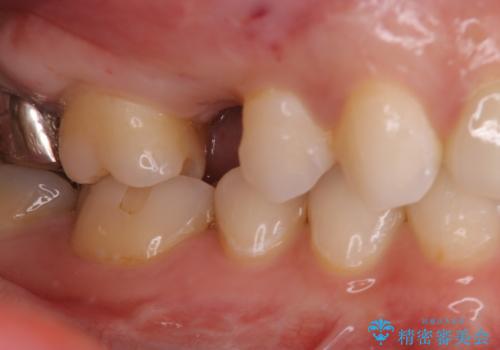

- 数年前に他医院で抜歯したままで過ごし、今回歯を入れたいとのことで来院された患者様です。

治療回数を短くしたいと1DAYインプラントを希望されました。

インプラント埋入手術は1回で全て行い、2ヶ月後にはセラミック治療で、審美回復と機能回復をしました。